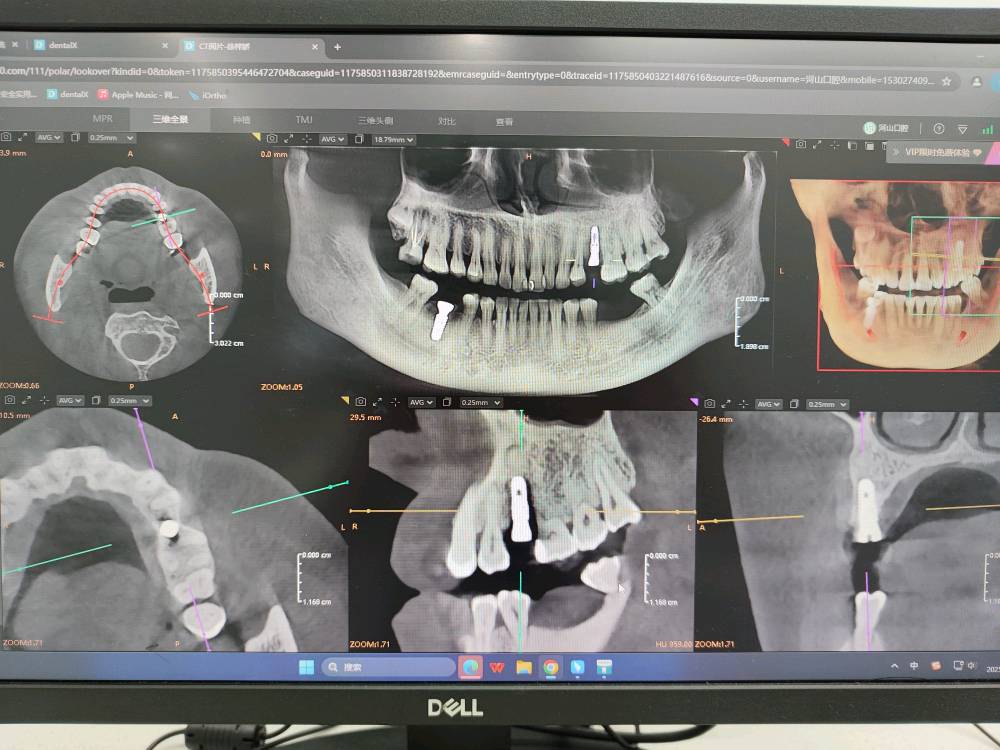

- 影像学检查:拍摄口腔全景片或CBCT(三维影像),评估骨量、神经位置。

- 制定方案:根据检查结果,选择种植体品牌,并制定个性化种植计划,安排手术时间。